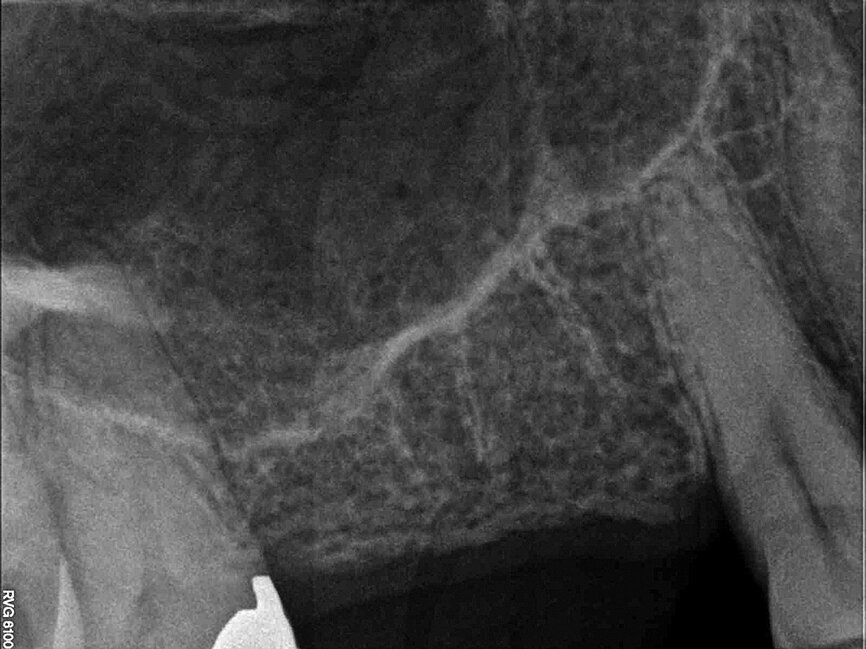

Fig. 2: Pre-op radiograph.

The scan was taken with a Morita 3-D CBCT system, which provides high definition, distortion-free images for accurate diagnosis and planning. Radiographic and CBCT examination revealed approximately 9 mm of bone depth, from the crest of the ridge to the floor of the maxillary antrum, in the upper right second premolar site, and no more than 5 mm bone depth in the first molar site. Planning took place immediately after the scan, with the patient present, so she could see the proposed treatment on the Navident software. She felt reassured by the care being taken to achieve optimum implant positioning, with minimal risk of potential complications, and was extremely impressed with the technology.